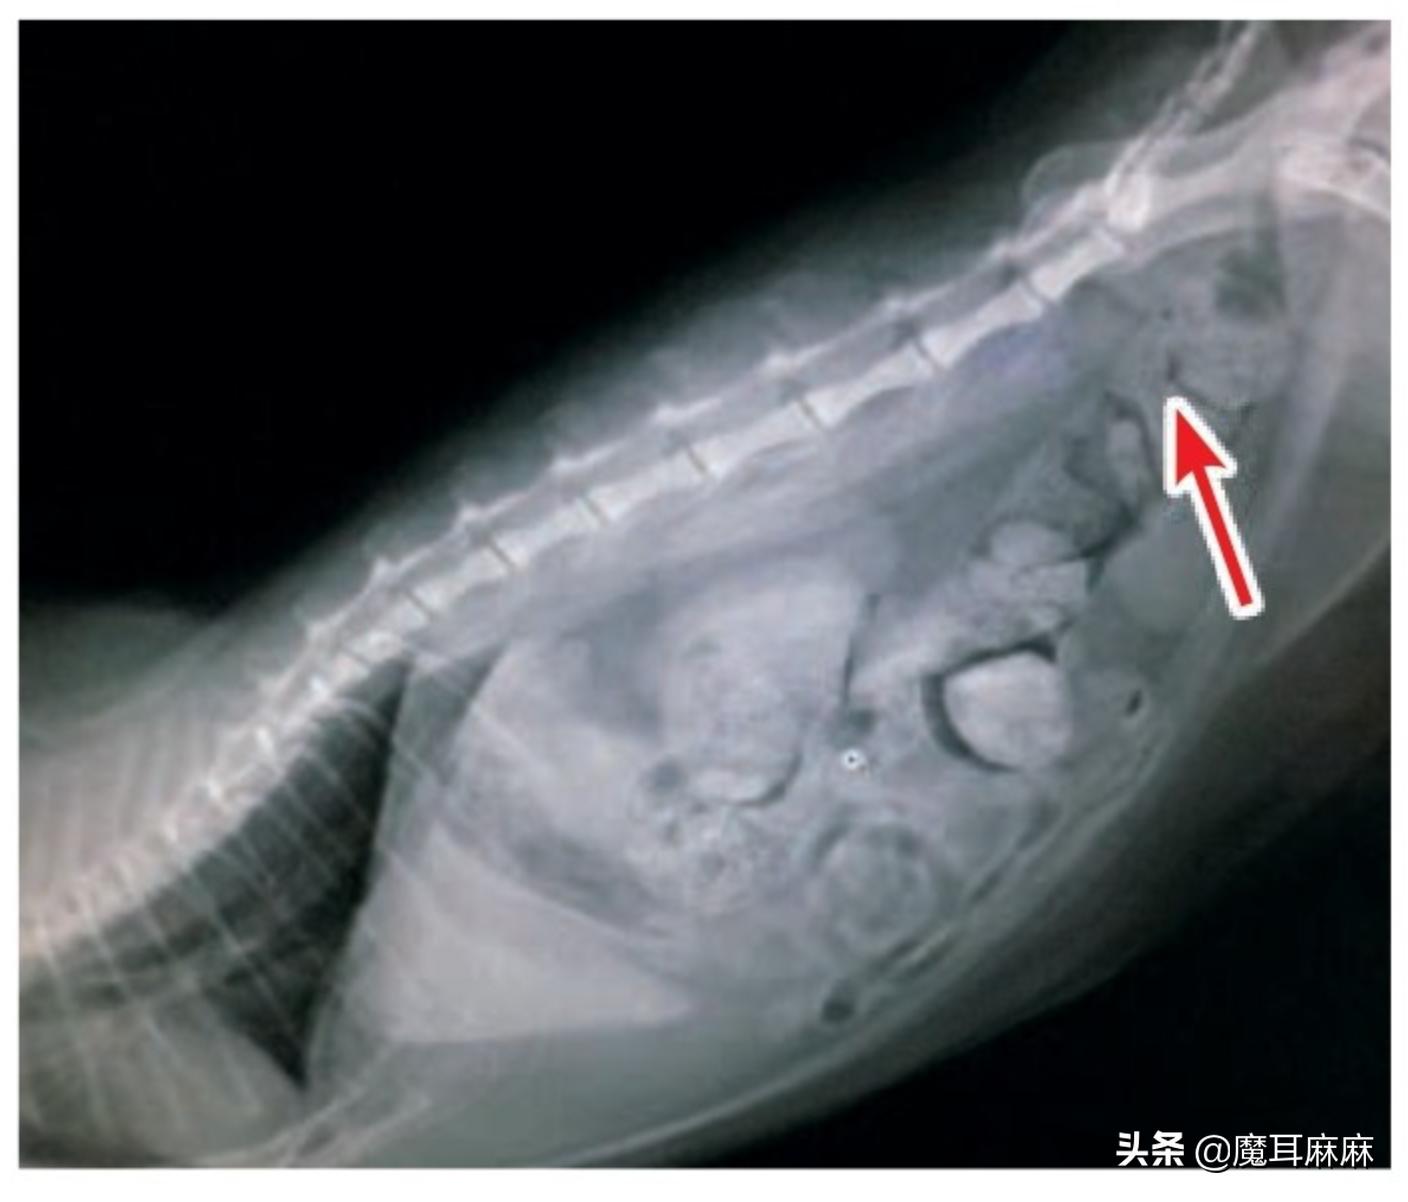

猫咪每天的排便量会因吃入食物的量和成分、体重、运动量以及喝水量而有所不同,如果能每天都排便是最理想的状态。老年猫或是因疾病造成的运动量不足、喝水量不够或是肠道蠕动的运动性变差都有可能造成便秘。另外,有些猫会因为异食癖而吞入塑胶、布料、头发以及毛球,或是摄取过多的钙,而导致粪便较硬。因为发生交通意外造成的脊椎骨盆损伤、先天性脊椎骨盆变形,也可能造成猫咪无法正常排便而形成便秘。肛门囊腺破裂的猫咪也会因为疼痛引起排便困难,容易形成便秘。

X光可以看出来 有很多粪便堆积